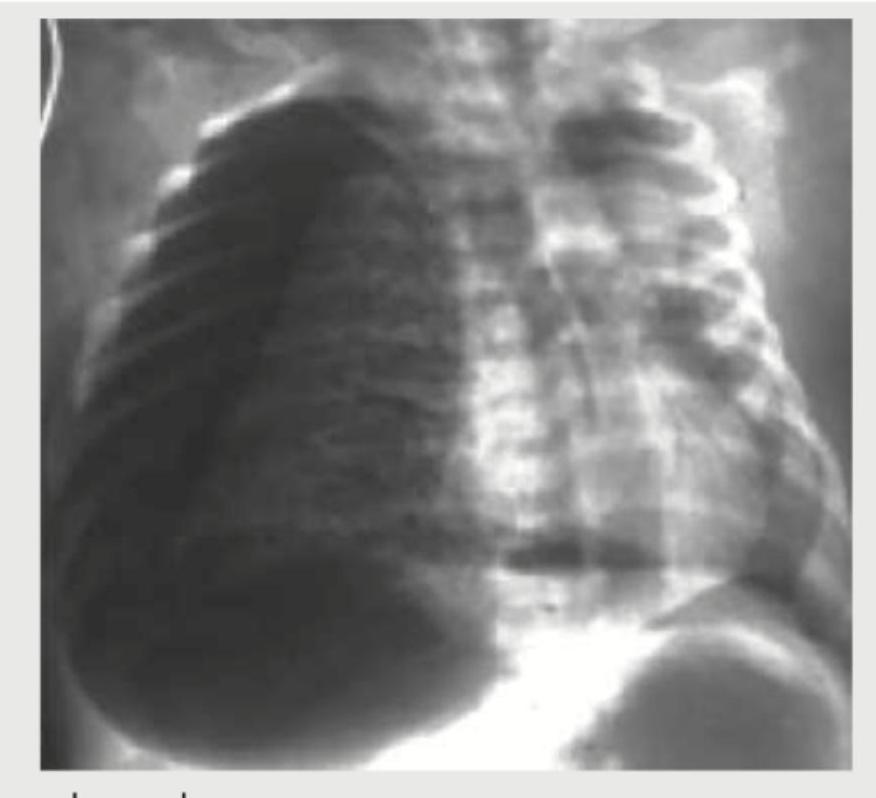

A 1-week-old neonate presents with anoxic spells and single S2. CXR shows all except:

Explanation: ***Pulmonary plethora*** - Pulmonary plethora, or **increased pulmonary vascular markings**, indicates increased blood flow to the lungs, which is not characteristic of Tetralogy of Fallot as it involves **pulmonary outflow obstruction**. - Tetralogy of Fallot leads to **decreased pulmonary blood flow**, resulting in **pulmonary oligemia** (reduced vascular markings) on CXR. *Boot-shaped heart* - This is a classic radiographic finding in **Tetralogy of Fallot** due to **right ventricular hypertrophy** and an upturned cardiac apex caused by **pulmonary hypoplasia**. - The image appears to show early signs of a boot-shaped heart (Coeur en sabot), consistent with the clinical picture of a cyanotic neonate with anoxic spells. *Right-sided aortic arch* - A **right-sided aortic arch** is seen in approximately 25% of patients with Tetralogy of Fallot and is a recognized associated anomaly. - While not universally present, its occurrence is significant enough to be considered a feature of the condition, making it a possible finding. *Right ventricular hypertrophy* - **Right ventricular hypertrophy** is one of the four defining features of **Tetralogy of Fallot** (together with ventricular septal defect, pulmonary stenosis, and an overriding aorta). - While not always directly visible as an enlarged chamber on a CXR, its presence is inferred by the **boot-shaped heart** configuration and the physiological adaptations to pulmonary outflow obstruction.